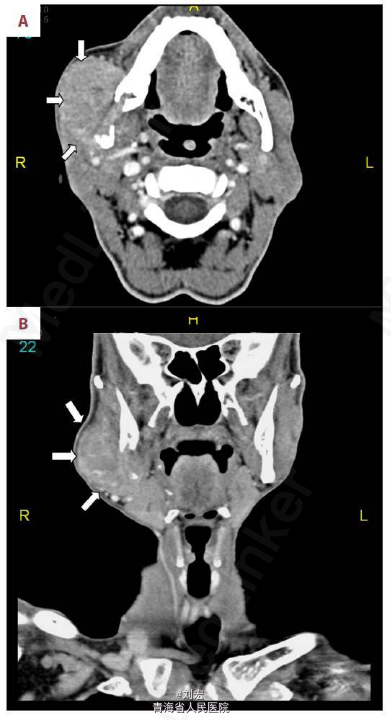

查体:右侧面部腮腺肿大,质硬伴轻压痛,肝脾肿大,移动性浊音阳性。辅查:腹部CT提示肝硬化、门脉高压和肝脏右叶的多中心肝细胞癌(图2)。颈部 CT 扫描提示右侧下颌角溶骨性破坏病灶(图3)。右侧腮腺切片活检和组织病理学检查,提示转移性肝细胞癌。